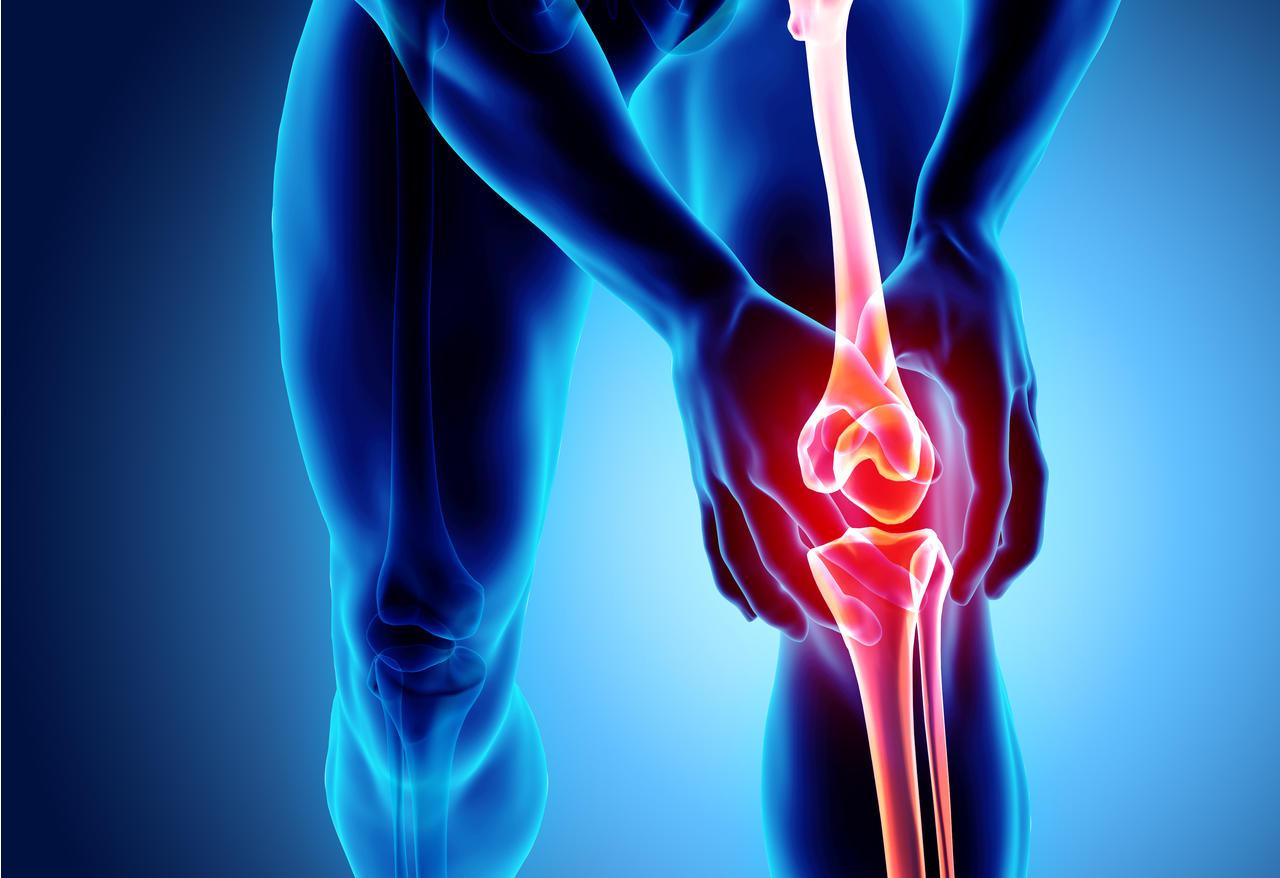

The regenerative medicine (bone and joint) market comprises products such as stem cell therapies, tissue-engineered products, and bone graft substitutes that help regenerate the damaged tissue and improve musculoskeletal disorders and injuries. Regenerative medicine offers advantages such as minimized surgical interventions, reduced pain and recovery time, and improved quality of life for...